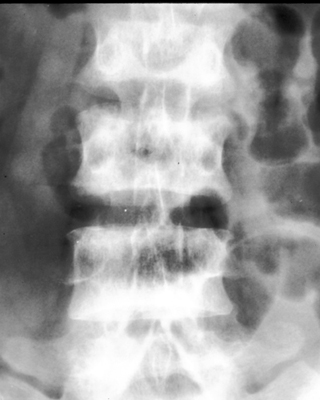

Diagnosis:Chronic renal failure Discussion:Roentgenographic appearance of increased density in the upper and lower zones of the vertebral body in a striated appearance. The pattern was similar to the alternating colors of the rugby players jersey design popular at the time of the description of this entity. Rugger Jersey spine is typically reserved for secondary hyperparathyroidism. References: